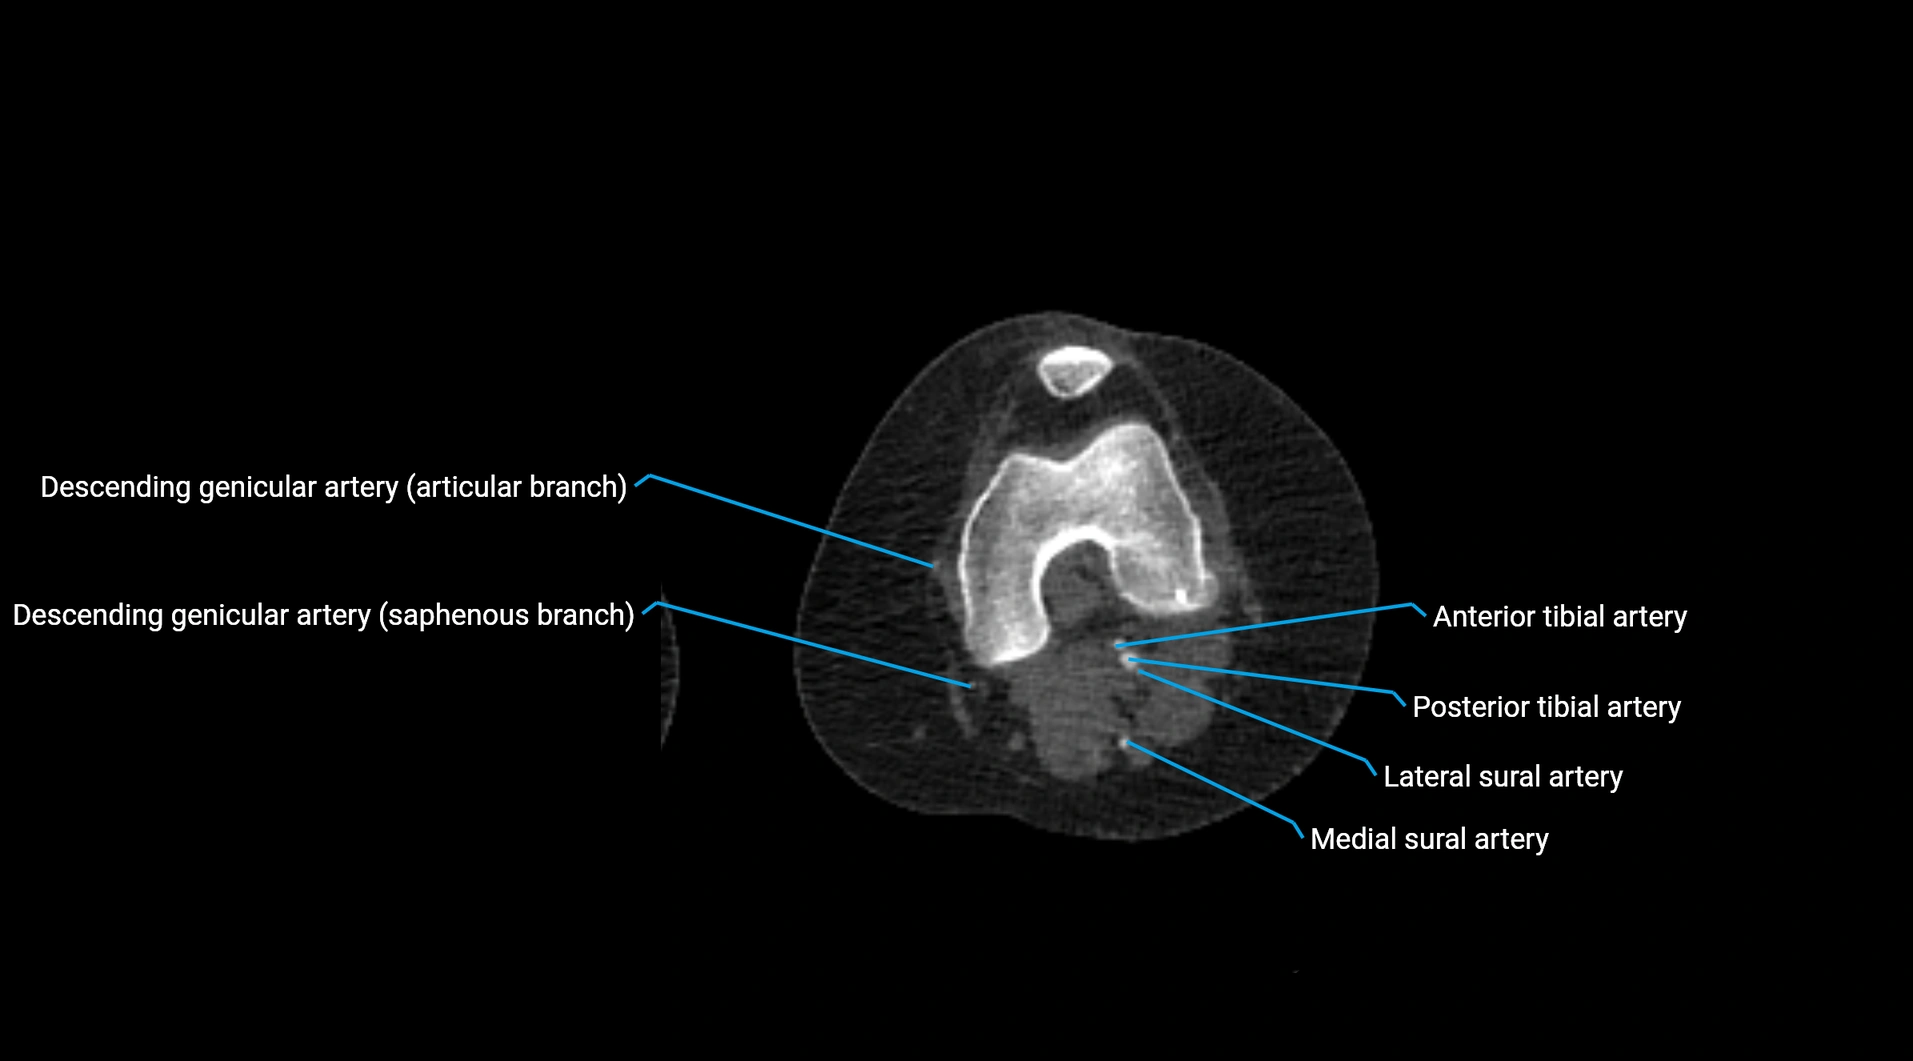

Contrast-enhanced CT (CTA):

• Gold standard for abdominal aortic imaging

• Provides excellent detail of lumen, wall, aneurysm, thrombus, and branch vessels

• Multiplanar and 3D reconstructions help in aneurysm measurement, stent graft planning, and dissection evaluation

• Detects acute rupture, traumatic injury, or occlusion with high sensitivity